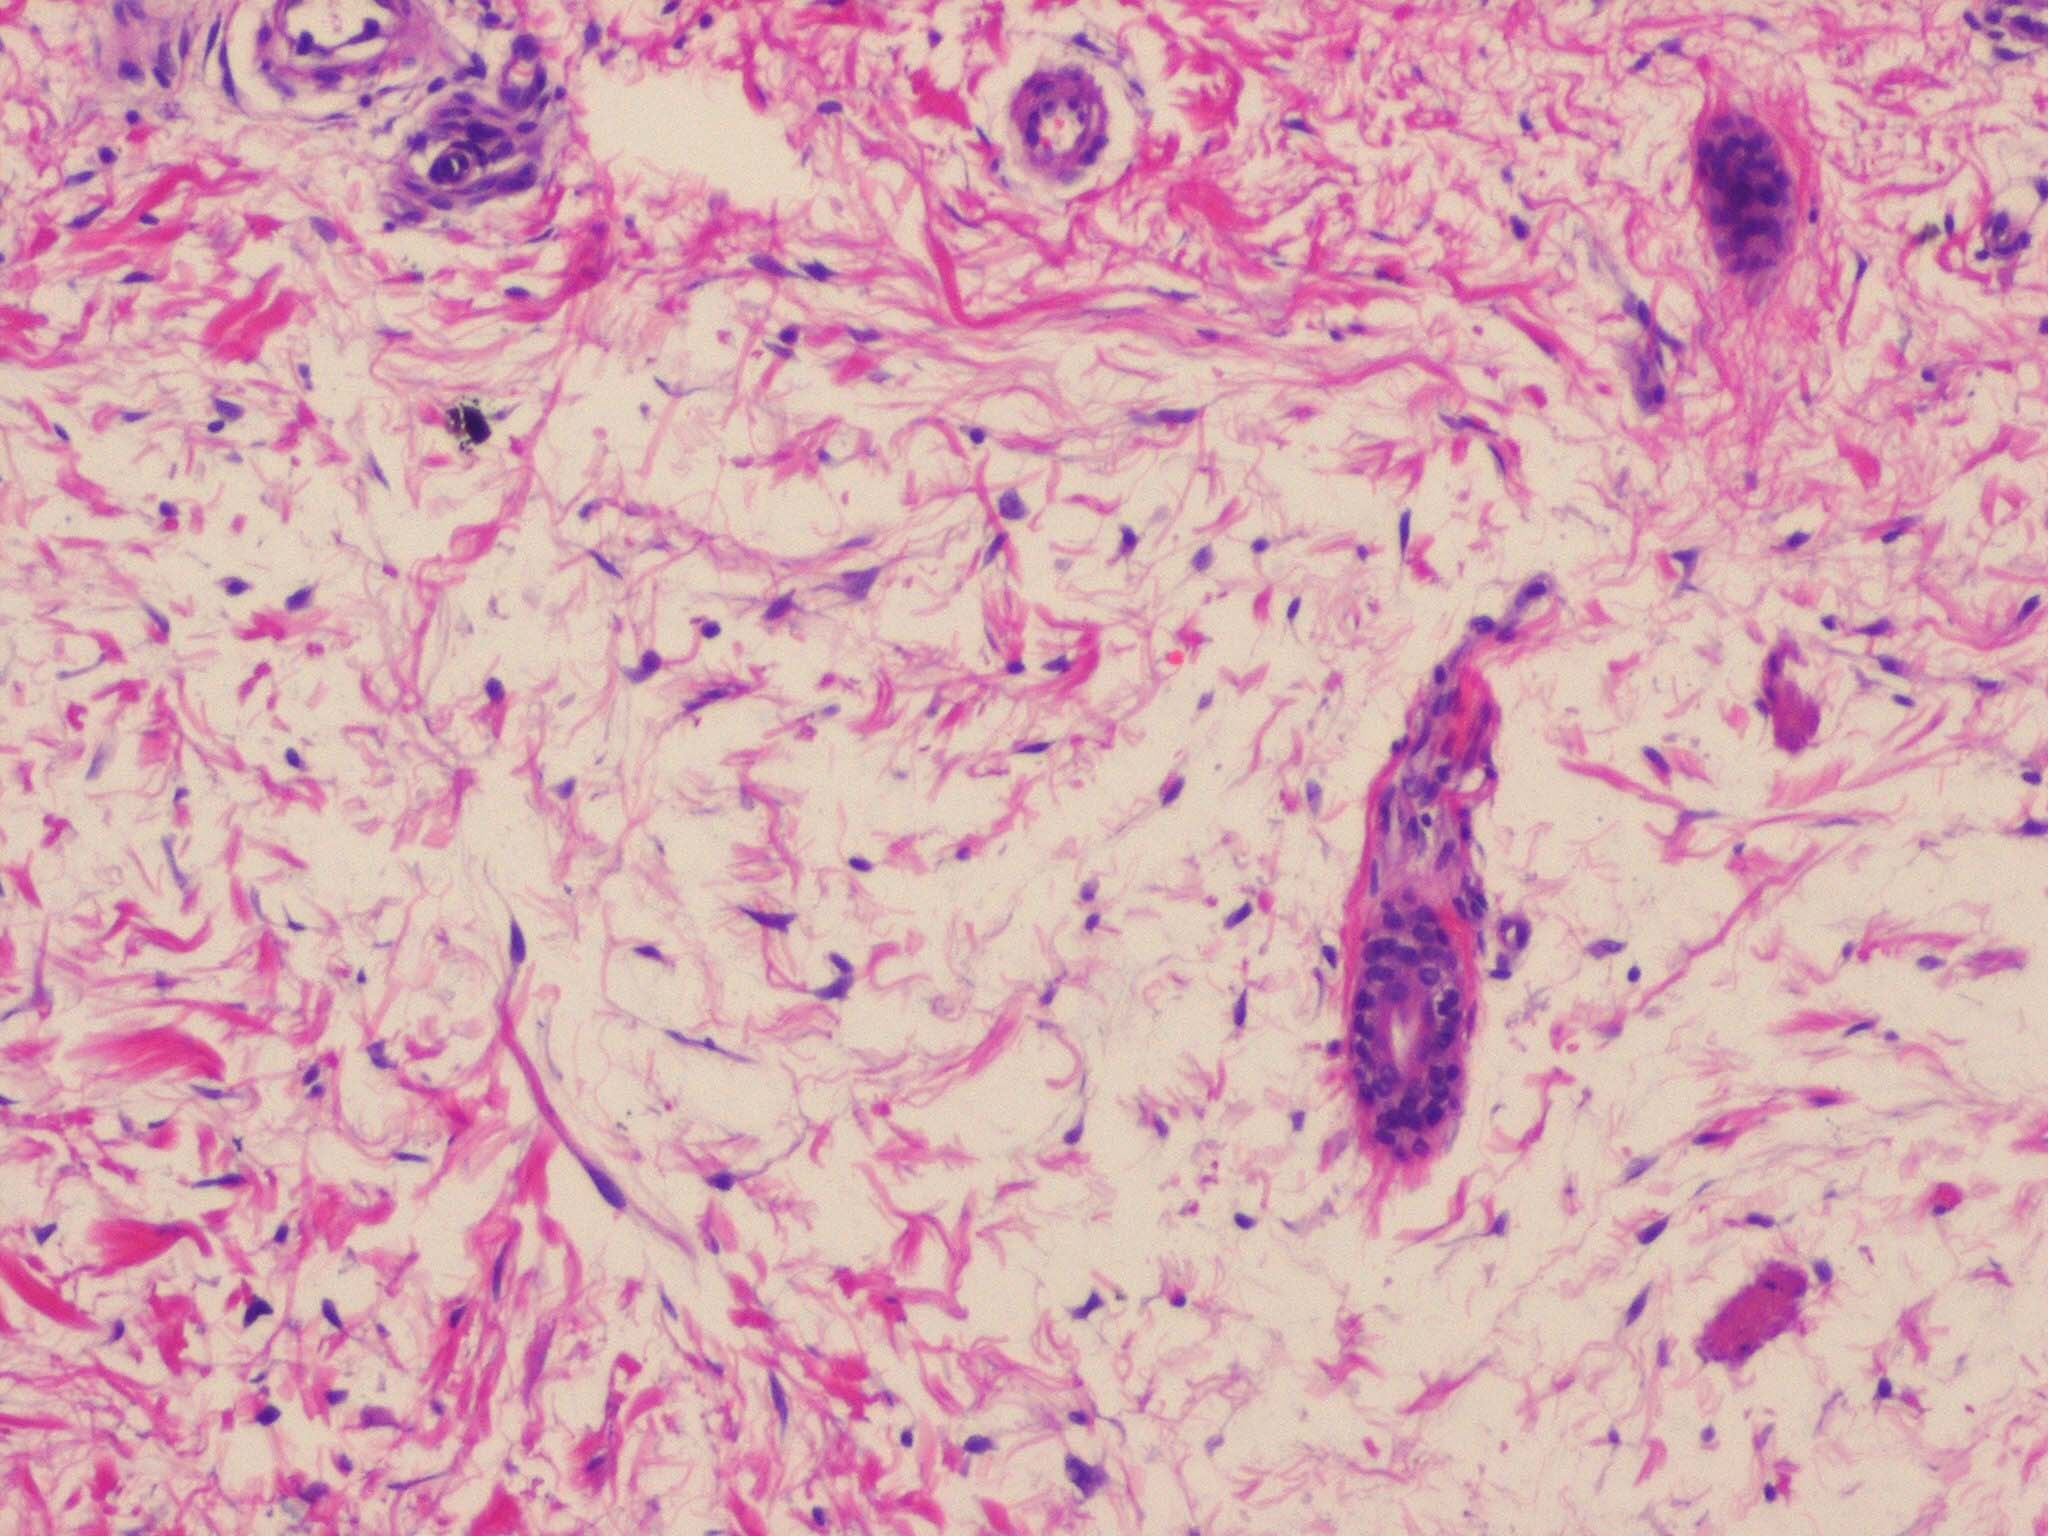

The epidermis and papillary dermis are usually normal. Mucin in large amounts is present in the dermis,

particularly in the upper half . As a result, the dermis is greatly thickened. The mucin occurs not only as individual threads and granules but also as extensive deposits resulting in the splitting up of collagen bundles into fibers and wide separation of the fibers. As a result of shrinkage of the mucin during the process of fixation and dehydration, there are empty spaces within the mucin deposits. The number of fibroblasts is not increased as a rule, but in areas where there is much mucin, some fibroblasts have a stellate shape and are then referred to as mucoblasts . A perivascular infiltrate of lymphocytes may be seen in some cases, and mast cells are moderately increased in number .